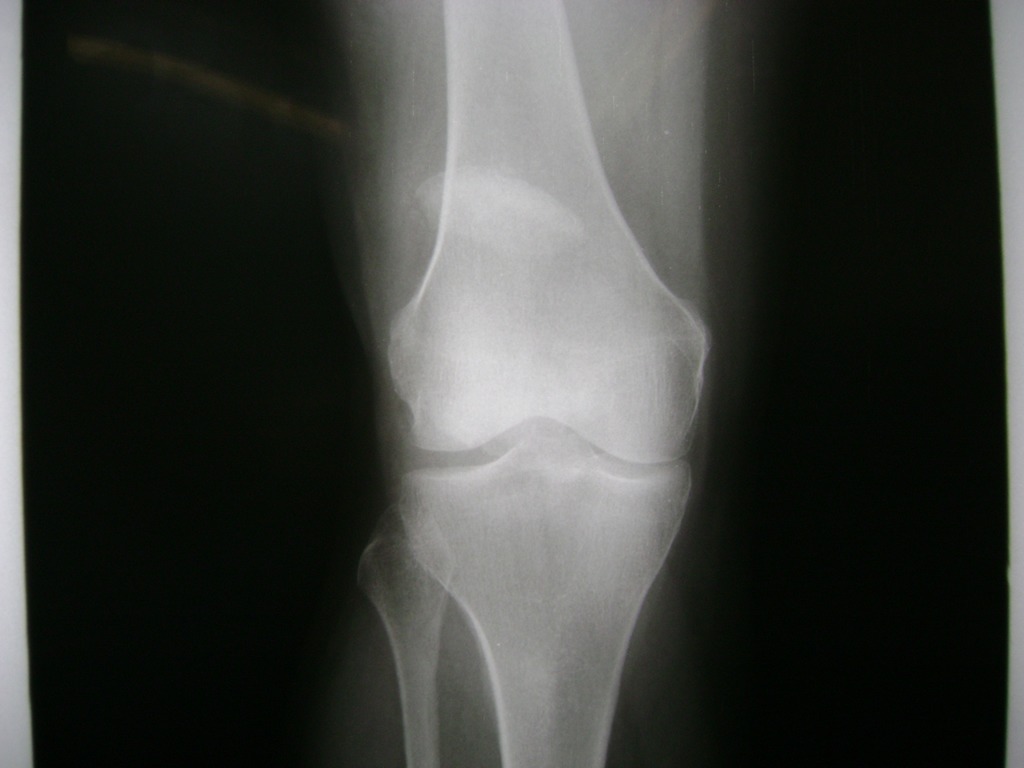

Cirugías de Rodillas

La artroscopia de rodilla es un cirugía en el cual la estructura interna de la articulación es examinada ya sea para realizar un diagnostico o para realizar un tratamiento, este procedimiento se realiza utilizando un instrumento parecido a un pequeño tubo llamado artroscopio.